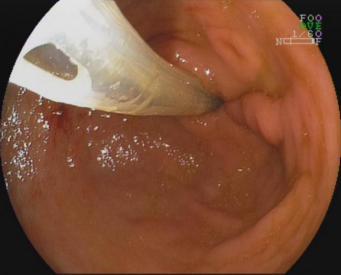

九、经口内镜下食管括约肌切开术(peroralendoscopicmyotomy,POEM)

POEM是治疗贲门失弛缓症的内镜新技术,基本取代传统的胸外科开胸食管肌切开术,成为首选的治疗方式。

贲门失弛缓症食管紧闭 食管粘膜切开建立隧道

食管肌切开 金属夹闭合切口